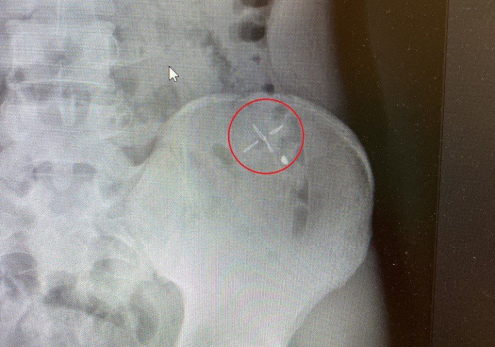

Российские врачи спасли 19-летнего парня с металлическим обломком в животе. Все произошло, когда молодой человек косил на даче траву, не используя спецодежду. В процессе работы от садового триммера отскочила небольшая часть и вонзилась в живот.

Как сообщает Минздрав, пациента доставили в Каширскую больницу с кровоточащей раной. Чтобы достать обломок врачи решили проводить оперативное вмешательство.

- Мы провели исследование раневого канала, затем удалили инородное тело, которое прошло через несколько слоёв кожи, и наложили швы. Еще несколько миллиметров и могло произойти повреждение брюшины, которое грозило травмой внутренних органов, - рассказал заведующий хирургическим отделением Александр Страчук.

Сейчас пациент чувствует себя хорошо. А специалисты тем временем напоминают, что не стоит пренебрегать средствами защиты даже при работе в собственном саду или огороде.

фото: Минздрав